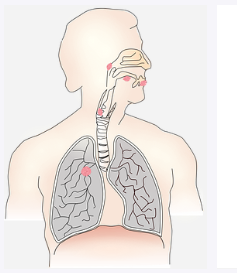

폐암 초기증상 두 번째는 객혈입니다. 폐에 종양이 생길 경우 초반에 증상이 없지만 기관지 근처에서 종양이 생기면 객혈이 나올 수 있습니다. 기관지 쪽에는 혈관이 있기 때문에 기침을 할 때 객혈이 나올 수 있습니다. 또한 가래를 뱉을 때 객혈이 나온다면 이 또한 의심해 볼 필요가 있습니다.

폐암 초기증상 세 번째는 이상한 숨소리입니다. 숨을 쉬는데, 평소와 다른 소리가 나는 것 같다면 의심해 봐야합니다. 종양이 기도 근처에 자라고 있어서 숨소리가 이상하게 들릴 수가 있는 것이죠.